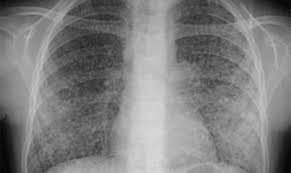

Chụp X quang là kỹ thuật chụp được sử dụng nhiều nhất trong y khoa, giúp bác sỹ có thể đánh giá, phát hiện những triệu chứng bất thường của phim chụp X quang phổi, từ đó có thể giúp các bác sỹ lâm sàng đưa ra chẩn đoán sơ bộ. Bài viết sẽ cung cấp thông tin về những tổn thương cơ bản của phổi phát hiện trên X quang.

Căn cứ vào mức độ cản tia X của tổn thương, các tổn thương ở phổi được chia làm ba dạng là hình mờ, hình sáng và hình mờ - sáng kết hợp.

Có thể thấy, với những bất thường xuất hiện khi chụp X quang phổi, bác sỹ có thể phát hiện, chẩn đoán được tổn thương cơ bản ở bệnh phổi dựa trên những dấu hiệu cũng như kinh nghiệm của mình.